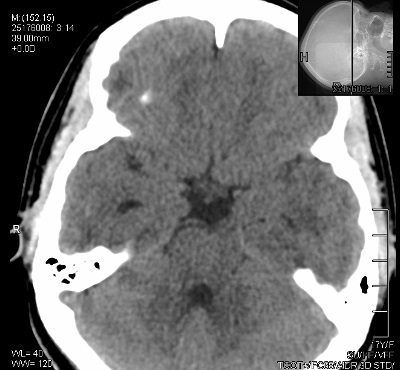

ÇEKİLECEK ALAN: Çekeceğimiz alan anteroir klinoidlerden başlayıp posterior klinoidler ve dorsum sella bitimine kadar olan bölgedir. Fov alanımızı ne kadar kısık ayarlarsak görüntümüz o kadar büyük gelecektir.

GÖRÜNEN YAPILAR: Hipofiz bezi , Sella tursika , Klinoidler ...

ÖRNEK KESİT: Fotoğrafları büyütmek için üzerlerine tıklayınız.